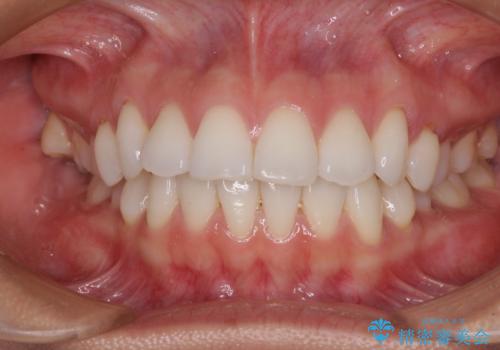

【モニター】インビザラインで口を閉じやすく

- 前に出ている上顎前歯が気になるとのことで来院された患者様です。

インビザラインを用い、IPR(歯と歯の間を削る)と歯列全体を後方に移動させることで、可能な限り前歯の突出感を改善することとしました。

元々の歯列も整っており、横顔の印象の出っ歯ではなかったため、仕上がりに満足できない可能性があると心配しておりましたが、口が閉じやすくなり、患者様には大変満足していただきました。